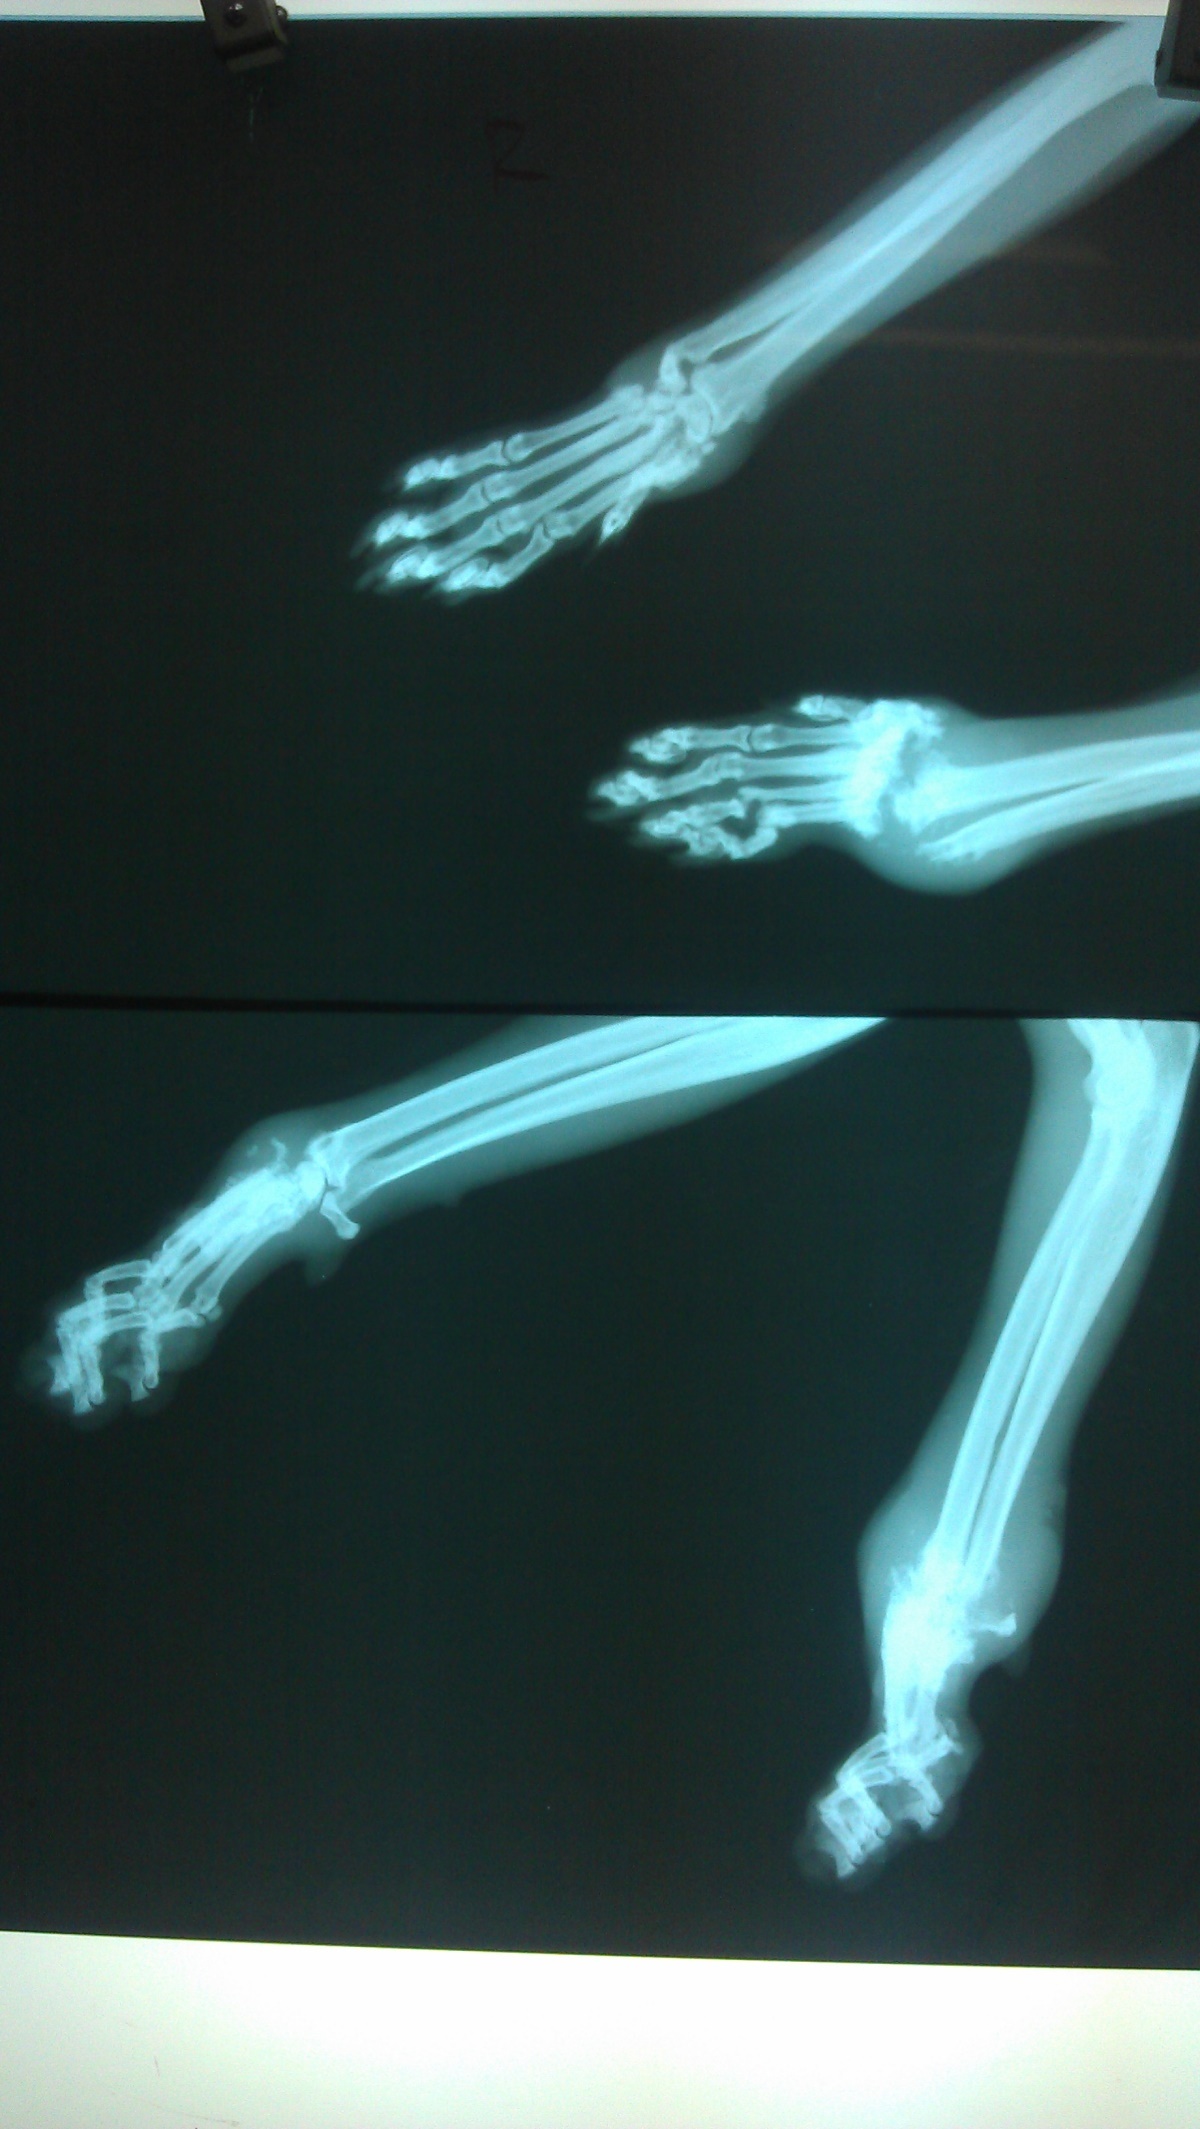

經聯絡由志工張先生協助,在兩天後捕捉,送醫檢查發現前肢疑似骨折,前肢x光片顯示左前肢腕骨已完全被蝕骨細胞破壞吸收,結構完全破壞,評估可能無法保留,右前肢部份趾骨及腕骨亦因骨折而遭破壞, 但大致結構仍完整,為了日後貓咪的生活品質著想,我們以保住貓咪雙腳為努力的目標,經過四個月漫長的醫療,貓咪的腳得以保存,雖然不會像正常貓那樣靈活,但行動自如,也由附近愛心人士照顧中,很感謝醫師大力幫忙,在醫療費用上給予極大的優惠。